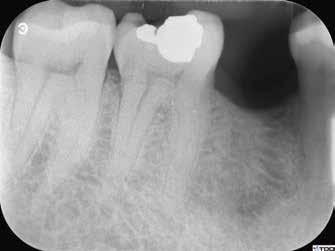

1. a–g. ábrák: A direkt pulpasapkázás lépései. Kiindulási bitewing-felvétel: A meglévő restaurátum közel helyezkedett el a pulpakamrához (a). Kiindulási periapicalis felvétel: Nincs periapicalis elváltozás fennállására utaló jel (b). A pulpaexpozíció (c). A vérzéscsillapítás céljából 20 másodpercen keresztül steril vattagombóccal történő kompressziót követően látható pulpaseb (d). A pulpasapkázás céljából behelyezett anyag, a széli részek tisztázása előtt készült felvétel (e). A röntgenárnyékot nem adó ideiglenes tömés behelyezése után készült felvétel (f). Az első ülés végén a röntgenárnyékot nem adó ideiglenes töméssel ellátott fogról készített röntgenfelvétel (g).

2. ábra: A hat hónapos kontroll alkalmával készített röntgenfelvételen vastag dentinhíd látható a pulpasapkázó anyag alatt.

3. ábra: A hároméves kontroll alkalmával készített röntgenfelvételen megfigyelhető a restaurátum pontos illeszkedése.

6. a–d. ábrák: A bal alsó második nagyőrlőfogon (3.7) kialakított konzervatív hozzáférési nyíláson keresztül végzett endodonciai kezelés lépései. A mezialis gyökér jelentős mértékben görbült. A gyökértömés hidraulikus kondenzációs technikával készült.

8. ábra: Egy konzervatív endodonciai kezelést bemutató videó (https://youtu.be/M87d_Ycitcg).

7. a

b. ábrák: A jobb alsó első nagyőrlőfogon (4.6) lévő cirkóniumkoronán keresztül elvégzett endodonciai kezelés. A hozzáférési nyílás kialakítása a lehető legkonzervatívabb módon történt. A gyökértömés hidraulikus kondenzációs technikával készült.